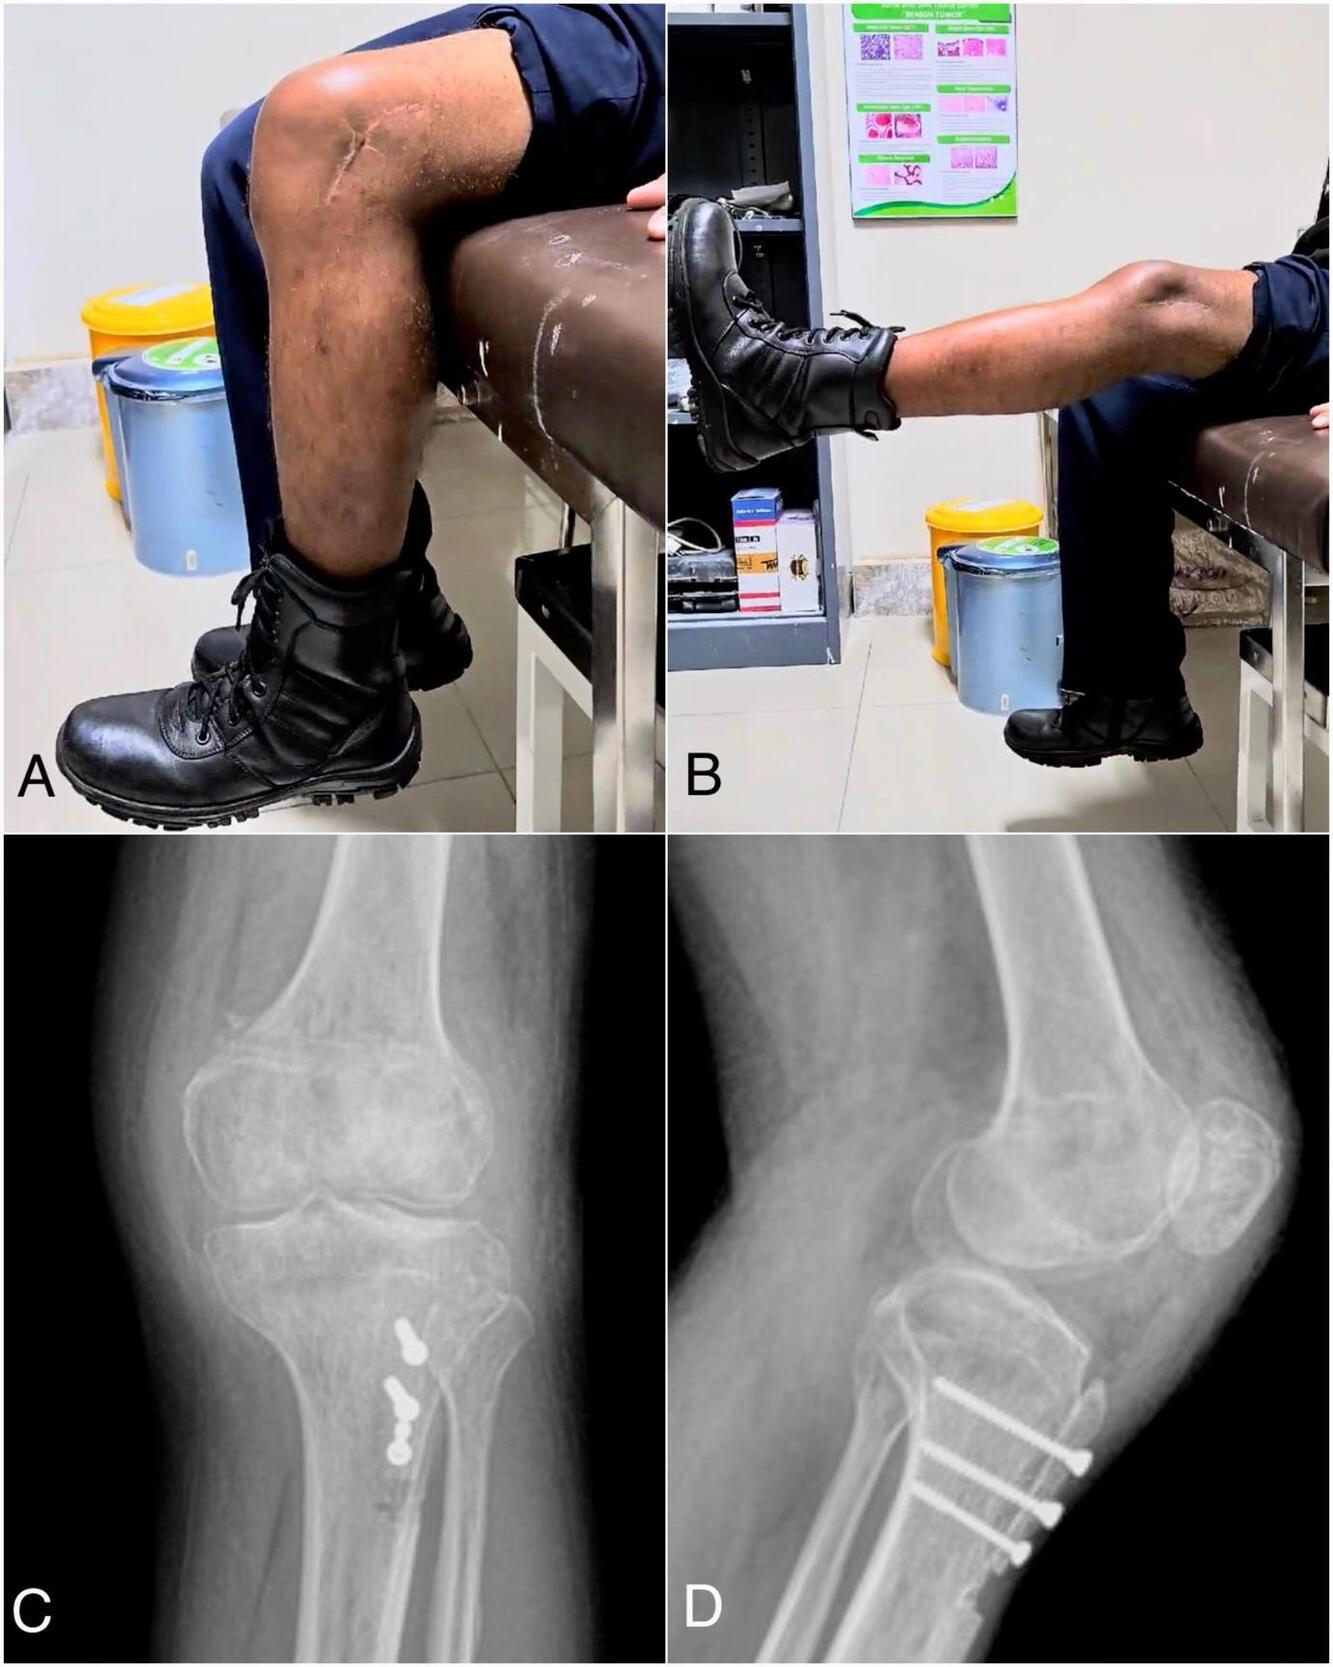

Following proximal and distal realignment, knee flexion-extension was performed to ensure optimal patellofemoral tracking. The surgery was completed (Fig 3D) and finalized with soft tissue and skin closure. After treatment, a knee brace was used to immobilize the patient’s knee for six weeks, at which point the rehabilitation procedure began. The patellar position then was confirmed by knee x-ray following the procedure (Fig 4), and it was supported by the Insall-Salvati ratio of 1.2 and the Caton-Deschamps ratio of 0.8.

Follow-up conducted at six months and twenty months. The patient’s anterior based patellar position well-maintained. The physical examination indicated a flexion range of 100 degrees improve into 115 degrees and an extension maintain range of 0 degrees from the horizontal axis (Fig 4). Evaluation with clinical scoring showed an improvement, as indicated by the Tegner Lysholm score of 85 and the IKDC score of 80.5 (Table 1). Patient was satisfied with the results and able to go back to his regular activities with no recurrence dislocations.